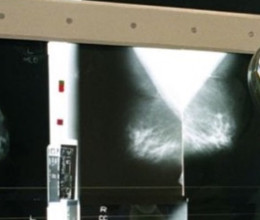

mellrák